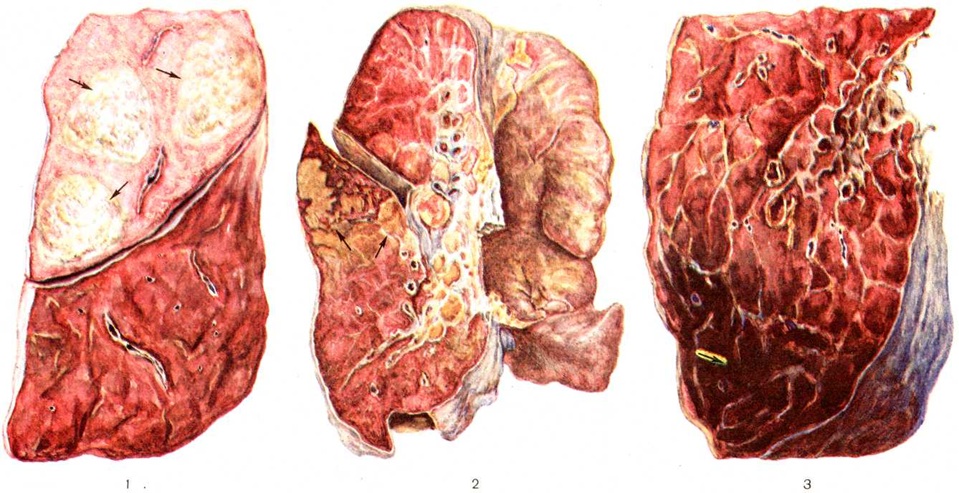

По локализации и объёму поражения лёгких различают следующие формы Пневмония: долевую, или лобарную, Пневмония— при поражении целой доли лёгкого (в этом случае применяют термин «крупозная пневмония»); очаговую Пневмония— при поражении части сегмента, целого сегмента или нескольких сегментов лёгких. В связи с тем, что при очаговой Пневмония обычно поражаются и бронхи, в качестве синонима используется термин «бронхопневмония». Воспалительный процесс при очаговой Пневмония чаще локализуется в нижних долях лёгкого, особенно справа, иногда бывает двусторонним. В случае слияния ряда очагов создаётся впечатление о поражении целой доли (цветной рисунок 1), что обозначается термином псевдолобарная Пневмония (например, при Пневмония, вызванной палочкой Фридлендера). При локализации патологический изменений в строме лёгкого Пневмония называют интерстициальной или межуточной; такие изменения, однако, редко бывают воспалительными в полном смысле слова, как правило, это лимфогистиоцитарно-плазмоцитарные, чаще периваскулярные и перибронхиальные инфильтраты, являющиеся местным проявлением иммунологический реакций. При поражении в основном респираторных отделов лёгких патологоанатомически выделяют альвеолиты — форму Пневмония, характеризующуюся выраженными изменениями альвеолоцитов.

Макроскопически очаги бактериальной Пневмония могут иметь разный характер в зависимости от стадии процесса. На ранних стадиях заболевания с поверхности разреза стекает большое количество мутноватой пенистой жидкости; отчётливо определяемых очагов уплотнения ещё нет. В разгаре процесса видны безвоздушные очаги уплотнения размером от нескольких миллиметров до десятков сантиметров в диаметре, чаще всего серого цвета. В случае примеси к экссудату фибрина поверхность разреза пневмонического очага мелкозернистая, в остальных случаях — гладкая. Если к экссудату примешиваются эритроциты, очаги Пневмония становятся серо-красными, красными и даже темно-красными. На поздних стадиях болезни при рассасывании выпота лёгкие приобретают обычный цвет, однако в течение некоторого времени остаются дряблыми.

В большей части случаев альтеративный компонент воспаления выражен слабо. Вначале отмечается только полнокровие структурных образований лёгкого, в которых находятся и размножаются бактерии. Вскоре возникает отчётливо выраженная фаза экссудации, которая начинается с выпотевания в полость альвеол плазмы крови — серозной жидкости; затем к ней присоединяется все возрастающее количество нейтрофильных лейкоцитов. При поступлении в очаг воспаления грубодисперсных белков крови происходит выпадение фибрина (рисунок 1). Пролиферативные изменения в подавляющем большинстве острых бактериальных Пневмония выражены незначительно. В том случае, когда бактерии, в частности стафилококки или стрептококки, образуют значительное количество токсинов, возникает некроз клеток экссудата и лёгочной ткани, резко повышается проницаемость кровеносных сосудов.

При пневмококковой Пневмония, в частности при её наиболее тяжёлом варианте — крупозной Пневмония, процесс начинается с развития небольшого очага серозного воспаления, располагающегося обычно в задних или в заднебоковых отделах лёгких, где содержатся пневмококки (рисунок 2, а). Патологический процесс распространяется прежде всего контактным путём и очень быстро захватывает значительную часть лёгкого — целую долю и даже несколько долей. Макроскопически лёгкое увеличено в объёме, его ткань резко отёчна и полнокровна. Эти изменения носят название стадии прилива.

В дальнейшем в экссудате нарастает количество нейтрофильных лейкоцитов, нередко одновременно с фибрином серозно-гнойный экссудат постепенно заполняет просветы альвеол (рисунок 2,6); последние достигают при этом размеров, которые они имеют на вдохе; пневмококки в это время фагоцитируются лейкоцитами и исчезают. При прогрессировании болезни более выраженные нарушения определяются на границе с неизменённой тканью органа. На разрезе лёгкое серого цвета с мелкозернистой или гладкой поверхностью, по консистенции напоминает печень (серая гепатизация лёгкого). У больных с повышенной проницаемостью сосудов к экссудату присоединяется большое количество эритроцитов, в результате чего лёгкое приобретает серо-красный или темно-красный цвет (красная гепатизация лёгкого).

В период выздоровления происходит рассасывание выпота; макроскопически в этот период лёгкие характеризуются пониженной воздушностью и эластичностью.

При очаговой пневмококковой Пневмония отмечаются сходные изменения, но с меньшей степенью выраженности.

Стафилококковая Пневмония имеет ряд особенностей. На ранних стадиях заболевания вокруг скоплений стафилококков появляется серозный или чаще серозно-геморрагический экссудат с небольшой примесью нейтрофильных лейкоцитов. В дальнейшем очаги воспаления приобретают характерное зональное строение.

В центре их содержится много стафилококков, возникают некротические изменения (рисунок 3, а), вокруг участков некроза накапливаются лейкоциты, которые фагоцитируют стафилококки. В периферических участках пневмонического очага альвеолы содержат фибринозный или серозный экссудат, в котором нет бактерий. При тяжёлом течении болезни (стафилококковой деструкции лёгких) в местах скоплений стафилококков на значительном протяжении происходит разрушение лёгочной ткани. Макроскопически в лёгких выявляются множественные мелкие, нередко сливающиеся очаги абсцедирующей Пневмония Они красного или темно-красного 4 цвета с желтовато-серыми участками расплавления в центральной части. Позднее здесь формируются абсцессы,. принимающие иногда хронический течение. При распространении инфекционные процесса на плевру и её деструкции возникает сообщение между полостью абсцесса, бронхами и плевральной полостью, развивается пиопневмоторакс (смотри полный свод знаний). Иногда в результате деструкции стенки бронха и проникновения воздуха в интерстиций возникает интерстициальная эмфизема.

Очаги Пневмония, вызванной палочкой Фридлендера, могут иметь долевой характер. Экссудат, а также выделяемая больным мокрота носят слизеподобный характер, поскольку палочка Фридлендера имеет слизистые капсулы; из-за небольшого содержания фибрина поверхность разреза лёгкого обычно гладкая. Характерно также образование обширных инфарктообразных некрозов лёгочной ткани в связи с тромбозом сосудов лёгкого. Макроскопически пневмонические очаги серовато-розового или реже серого цвета, нередко с красными участками кровоизлияний.